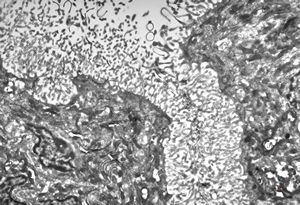

F,50y. | progressive multifocal leukoencephalopathy- viral particles in a glial cell

F,50y. | progressive multifocal leukoencephalopathy- viral particles in a glial cell

F,50y. | progressive multifocal leukoencephalopathy- viral particles in a glial cell